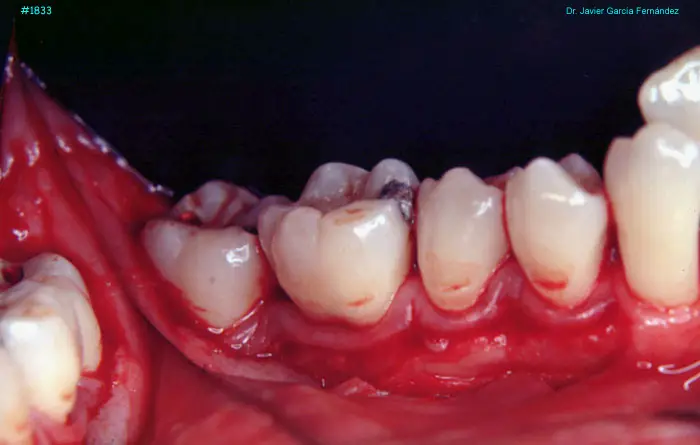

Atlas of Surgical Techniques in Periodontics. CASOS CLINICOS.

Atlas de Técnicas Quirúrgicas en Periodoncia

image 99